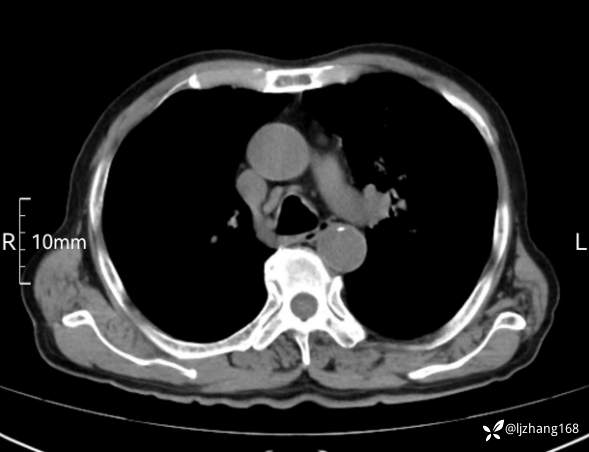

辅助检查:胸部CT:双肺肺气肿,间质性病变,血气分析:PH 7.413, PCO2 29.2mmHg, PO2,81.8mmHg,乳酸 3.3mmol/1,剩余碱-4.0mmol/1,HC03 18.8mmol/1。全血超敏C反应蛋白:超敏C反应蛋白 135.60 mg/L、 白细胞 14x19^9/L,中性粒细胞11.6x10^9/L。